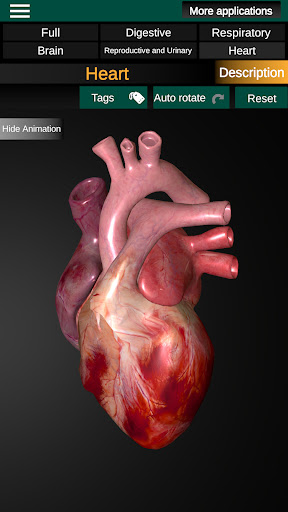

Internal Organs in 3D Anatomy لـ Vodafone Smart N9 Lite

(الأجهزة الداخلية في)

Internal Organs 3D Anatomy 3.4

يمكنك هنا تنزيل ملف حزمة تطبيق أندرويد "Internal Organs 3D Anatomy" الخاصة بجهازVodafone Smart N9 Lite مجانًا، نسخة ملف حزمة تطبيق أندرويد - 3.4 للتحميل على Vodafone Smart N9 Lite اضغط ببساطة على هذا الزر. إنه سهل وآمن. نحن نقدم فقط ملفات حزمة تطبيق أندرويد الأصلية. إذا انتهكت أية مواد موجودة في الموقع حقوقك قم بإبلاغنا من خلال